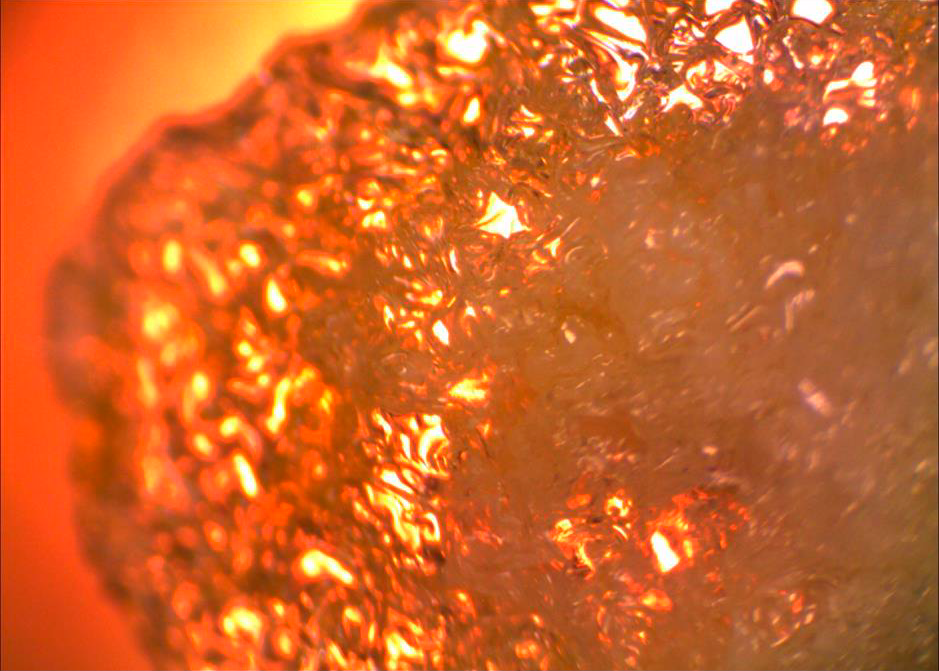

ТЕХНОЛОГИЯ ИЗГОТОВЛЕНИЯ СИСТЕМЫ VENASEAL™

| Специально подобранный состав |

Вид полимеризованного клея под микроскопом |